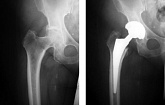

Еndoprosthesis of hip joint

In the late stages of arthrosis of the hip joint, medial fractures of the femoral neck in the older age group, the only way to recover is to replace the affected joint with an artificial joint - arthroplasty.

This method allows you to return the limb's limb, the full volume of movements in the affected joint, to save from constant pain and crunch during movements and, as a consequence, to return the patient to a full active life.

Below are presented X-ray photographs and photographs, illustrating the amount of motion in the affected joint before and after surgery.